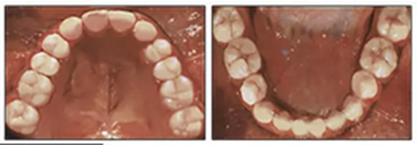

治療持續(xù)3年,患者始終保持積極和合作??谇恍l(wèi)生很好。患者和她的父母都對(duì)結(jié)果感到滿意。經(jīng)過24個(gè)月的保持后,咬合保持得很好(圖11 ; 圖12)。在上牙弓中,應(yīng)用固定舌側(cè)保持器以防止任何復(fù)發(fā)傾向。在下牙弓中,治療后拔除第三磨牙。